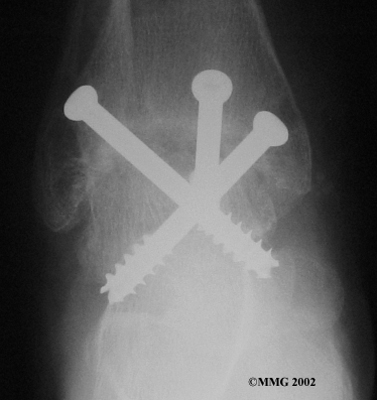

When the ankle joint becomes so painful that it is difficult to walk, surgery may be suggested to fuse the ankle joint. An ankle fusion is sometimes also called an ankle arthrodesis. In this operation, the three bones that make up the ankle joint (the talus, the tibia, and the fibula) are allowed to grow together, or fuse, into one bone. Once this is done the ankle no longer is able to move, but with a successful fusion the pain is gone. Most people with a successful fusion of the ankle are able to walk without much trouble, and in some cases it is almost impossible to tell that the ankle is stiff. But it is very difficult to run because you lose the ability to push off with the toes. The foot can't bend down.

The biggest problem with the older artificial ankle designs is that they loosened after a relatively short time and began to cause pain. When using the newer artificial ankle designs, surgeons have tried to solve this problem by actually fusing the tibia and fibula together during the operation and placing screws across the two bones. This has dramatically increased the success rate for the artificial ankle replacements done today. Many surgeons are now beginning to use the artificial ankle for post-traumatic arthritis instead of doing a fusion. Patients are able to keep the motion in the ankle and avoid some of the problems associated with the ankle fusion.